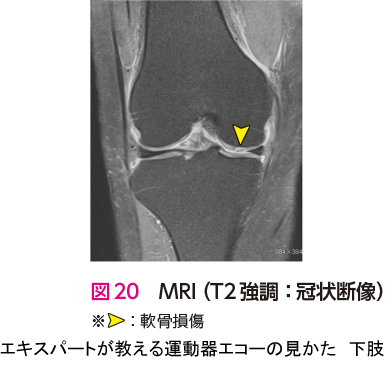

症例 7大腿骨内顆軟骨損傷

前述のように変形性膝関節症においてエコー検査の診断価値は低い.また,私自身も図18のエコー像で初診時に指摘できる自信はない.しかし,エコー検査を用いることで,注射をさまざまなポイントにエコーガイド下に安全かつ正確に打つことができる.そのため,私にとって形性膝関節症の診療におけるエコー検査は変必要不可欠なツールとなっている3).